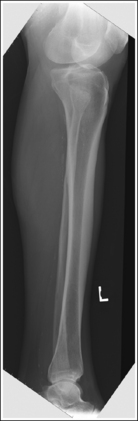

Image density is uniform across the lower leg.

The lower leg demonstrates a lateral projection. The distal fibula is superimposed by the posterior half of the distal tibia. The fibular midshaft is free of tibial superimposition. The tibia is partially superimposed over the fibular head, and the medial femoral condyle is demonstrated posterior to the lateral condyle if the leg is extended; the condyles are superimposed if the knee is flexed at least 30 degrees (compare Figure 6-67 and Image 51).

The distal and proximal ends of the fibula are superimposed by the tibia, whereas the fibular midshaft is free of superimposition. The knee is flexed approximately 45 degrees, and the femoral condyles are superimposed.

The distal fibula is situated too far posterior on the tibia, and the fibular head is free of tibial superimposition. The leg was externally rotated.